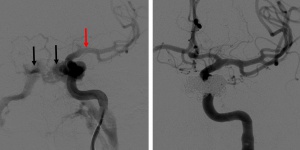

DSA: DSA remains the gold standard imaging modality in the diagnosis of direct and indirect CCFs. DSA is necessary to identify CCF location, arterial supply, flow rate, and venous drainage to classify the CCF and help plan for potential endovascular treatment strategies.[24][28]

Direct CCFs

Direct CCFs are unlikely to close spontaneously, and upfront treatment is indicated due to the risk of neurological deficits and worsening of venous congestion. Signs for urgent treatment of direct CCFs include visual impairment, progressive paresis of extraocular muscles, intractable orbital pain, bruit, and progressive exophthalmos.[14][18] Because direct CCFs originate from a defect in the cavernous ICA either from an aneurysm rupture or dissection, the goal of treatment is to cease flow into the CS and reconstruct the cavernous ICA. There are numerous endovascular techniques utilized to achieve this end including coil embolization (Figure 5), coil embolization with balloon remodeling of the ICA and coil embolization with stent-assistance.[35][36][37] Combined transvenous and transarterial approaches can be used to preserve the ICA and pack the CS with coils to stop flow. Liquid embolics such as Onyx (ethylene vinyl alcohol copolymer, Medtronic, USA) and n-butyl cyanoacrylate glue (n-BCA, Trufill, Cerenovus, USA) are less commonly used for direct CCF due to the risk of distal embolization into cerebral arteries and stroke. A large cavernous ICA defect such as that from a traumatic transection may require ICA sacrifice as a life-sustaining treatment. Parent vessel sacrifice (endovascular occlusion) may also be option in cases of recurrence if the patient passes a balloon test occlusion. Less commonly used approaches include covered stents, packing the cavernous sinus via open microsurgery, and cavernous ICA trapping with bypass.